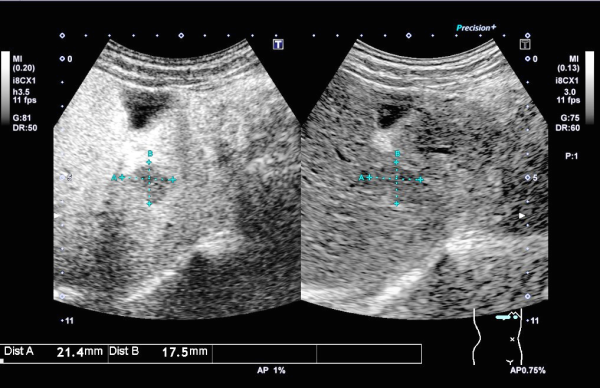

腹部超音波検査では上記に記載の臓器に病変がないかを調べる以外にも、肝臓の硬さを計測して数値化する肝エラストグラフィという検査や、肝臓の腫瘤に対して造影剤を用い、腫瘤が悪性腫瘍(肝細胞癌や転移性肝癌など)かどうかを調べる検査も行っています。また、超音波減衰法を用いて肝臓の脂肪量を数値化し、脂肪肝の程度を定量的に評価することができる装置を導入しています。

造影超音波検査